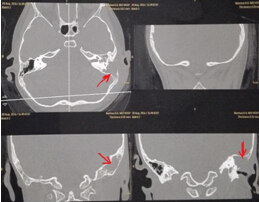

該患兒既往無中耳炎及耳流膿病史,僅表現(xiàn)為1個月前耳后稍有紅腫、疼痛,在當(dāng)?shù)蒯t(yī)院曾被診斷為“蚊蟲咬傷”所致,家長也未引起足夠的重視。近半月來,患兒耳后紅腫疼痛加重,遂到我市某三甲醫(yī)院就診,行高分辨率中耳乳突CT,發(fā)現(xiàn)側(cè)顱底、中耳乳突腔巨大新生物占位,乳突骨皮質(zhì)破壞吸收,并可疑耳后骨膜下膿腫形成。病情若進(jìn)一步發(fā)展,膽脂瘤破壞顱底骨質(zhì),將極有可能并發(fā)腦膜炎、腦膿腫,甚至出現(xiàn)敗血癥、腦疝等,危及生命。

3.術(shù)前CT2 4.術(shù)中術(shù)腔中的巨大膽脂瘤